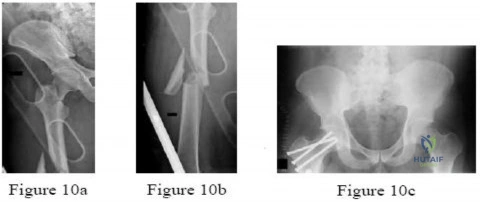

Question 1:

A 35-year-old male presents after an MVC with a systolic BP of 75 mmHg. Heart rate is 135 bpm. FAST scan is negative. Pelvic radiograph shows an APC-III pelvic ring injury. A pelvic binder is applied. Fluid resuscitation is initiated but his BP remains 80 mmHg. What is the most appropriate next step in management?

Correct Answer: Pre-peritoneal pelvic packing and external fixation

Explanation:

In a hemodynamically unstable patient with a pelvic ring injury and a negative FAST (ruling out intra-abdominal bleeding), the source of bleeding is likely the pelvis (venous or arterial). If the patient remains unstable despite a pelvic binder and initial fluid resuscitation, emergent mechanical stabilization (e.g., external fixation) and pre-peritoneal pelvic packing (PPP) is indicated. Currently, ATLS/AAOS guidelines support PPP + Ex-Fix as a rapid, definitive initial step in the operating room for venous bleeding (which accounts for ~80% of pelvic hemorrhage), often followed by angio if bleeding persists.

Question 21:

A 35-year-old male is brought to the ED after a high-speed motorcycle collision. He is hypotensive with a blood pressure of 80/40 mmHg and a heart rate of 125 bpm. Secondary survey reveals an unstable pelvis. A pelvic binder is to be applied. What is the correct anatomical landmark for optimal placement of the pelvic binder to effectively reduce pelvic volume?

Correct Answer: Greater trochanters

Explanation:

Pelvic binders are most effective at reducing pelvic volume and stabilizing the fracture when placed directly over the greater trochanters. Placing the binder too high (e.g., over the ASIS or iliac crests) is mechanically less effective and may paradoxically exacerbate the deformity.

A patient sustains an open pelvic ring injury in a high-speed collision. In the acute setting (within the first 24 hours), what is the most common cause of mortality in patients with this severe injury pattern?

Options:

Correct Answer: Exsanguinating hemorrhage

Explanation:

Open pelvic fractures are devastating injuries. In the acute phase (< 24 hours), the most common cause of mortality is exsanguinating hemorrhage arising from the highly vascular presacral venous plexus, major iliac vessels, and cancellous bone surfaces. If the patient survives the initial hemorrhagic shock, late mortality is most frequently due to sepsis and multi-organ failure.